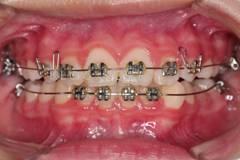

早期矯正中